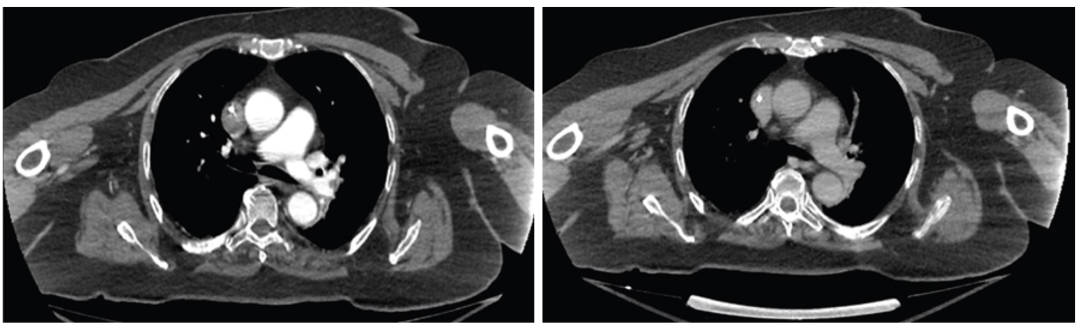

• Akura Medical 已于 2023 年启动首批“人体首例”(first-in-human)试验,用 Katana 系统治疗急性肺栓塞患者。初步数据显示,在数例患者中,手术后 48 小时通过影像学对比,右室/左室 (RV/LV) 比率明显恢复,血栓负荷显著降低,且未观察到重大不良事件。该结果被视为机械性取栓器械在 PE 治疗中的有力证明。

术后48小时显示血栓已溶解